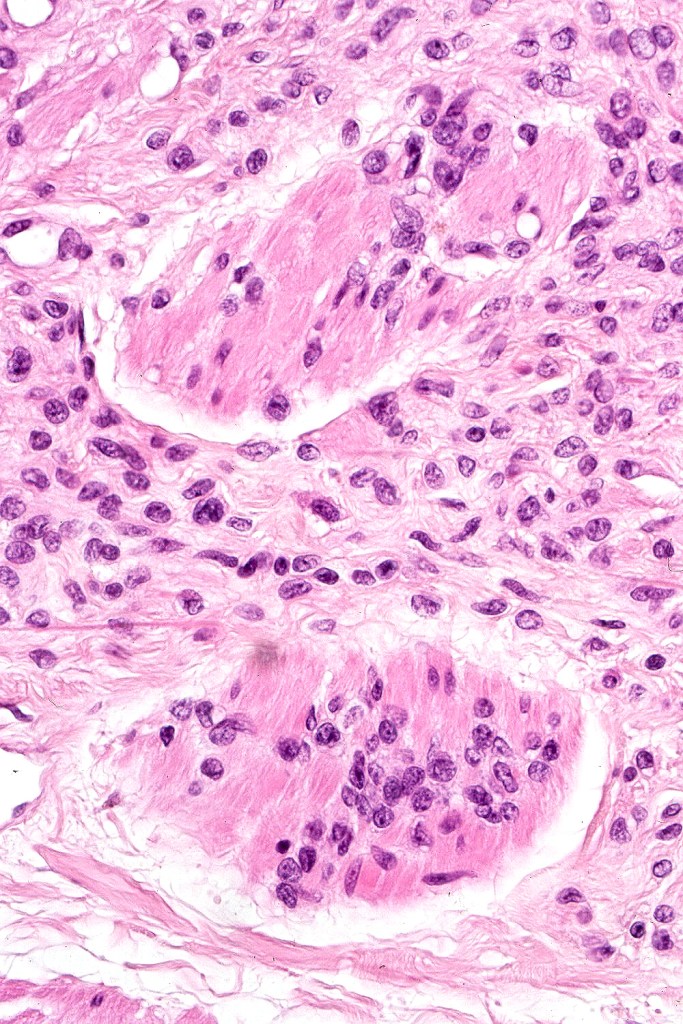

Melanoma arising in a congenital nevus

•Although the vast majority arise in giant forms, they may be encountered in smaller lesions & can be present at birth

•Develop in the dermal component

•Typical melanoma, nevoid melanoma, small cell melanoma, pleomorphic/anaplastic melanoma, melanoma with heterologous differentiation & malignant nerve sheath-like melanoma.

This melanoma arose in a small congenital nevus of the scalp. It metastasized widely. Varying features in different fields.